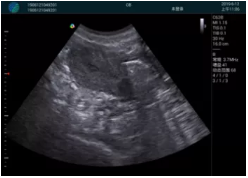

急診醫(yī)學(xué)的核心任務(wù)是對危重急的病人進(jìn)行快速診斷并進(jìn)行生命支持,在病人處理中的時(shí)效性和整體性顯得尤為重要。時(shí)效性是指要迅速及時(shí)的對病人的狀況作出初步診斷,同時(shí)采取相應(yīng)的有效措施,以挽救病人的生命。高效率的緊急救援,是政府機(jī)關(guān)、醫(yī)院對外形象展示的重要窗口,是衡量一個(gè)地區(qū)醫(yī)療技術(shù)及管理水平的重要標(biāo)志。為了適應(yīng)新時(shí)代急救系統(tǒng)的發(fā)展,新設(shè)備新技術(shù)在急救系統(tǒng)的應(yīng)用顯得越來越急迫??颠_(dá)i-M20便攜平板彩色超聲作為一種快速、無創(chuàng)的檢測設(shè)備在急救系統(tǒng)的應(yīng)用越來越普遍。

M20便攜超聲在臨床中的應(yīng)用:

可視化穿刺引導(dǎo)

M20實(shí)時(shí)引導(dǎo):向包塊后方間隙注射利多卡因

清晰顯示腺體內(nèi)低回聲快影,邊界清晰,包膜較光滑

確定進(jìn)針路徑并實(shí)時(shí)監(jiān)測抽吸針與腫塊位置關(guān)系

抽吸針進(jìn)入腫塊內(nèi)部進(jìn)行旋切

抽吸過程中可見腫塊明顯縮小,并根據(jù)腫塊位置改變針道位置

抽吸旋切后再進(jìn)行超聲復(fù)查,原腫塊區(qū)域未見殘留組織及出血

超聲引導(dǎo)下抽吸旋切取出的腫塊組織

病例二:

腺體內(nèi)部清晰顯示一低回聲塊影,形態(tài)不規(guī)則,邊界模糊,邊緣呈毛刺狀,內(nèi)部見砂礫樣鈣化

M20引導(dǎo)下穿刺活檢術(shù)

M20引導(dǎo)下平面內(nèi)穿刺取出的腫塊組織

M20查看:囊內(nèi)回聲均勻,邊界清晰,囊壁光滑

M20引導(dǎo)抽吸術(shù)后囊腫消失,原區(qū)域空腔形成,脂肪層與腺體層架構(gòu)發(fā)生改變

超聲以操作簡單、定位準(zhǔn)確、實(shí)時(shí)顯像、費(fèi)用低廉等優(yōu)勢,而成為麥默通乳腺活檢治療乳腺腫塊最常見的引導(dǎo)手段,已逐步在各大醫(yī)院開展此類手術(shù)。

2、超聲的可視化操作,能準(zhǔn)確的顯示病灶的位置、最大徑,選擇合適的刀具,決定切口的位置和方向,避開血管、減少出血危險(xiǎn)并實(shí)時(shí)觀察乳腺病灶的切割情況,避免造成腫塊組織殘留